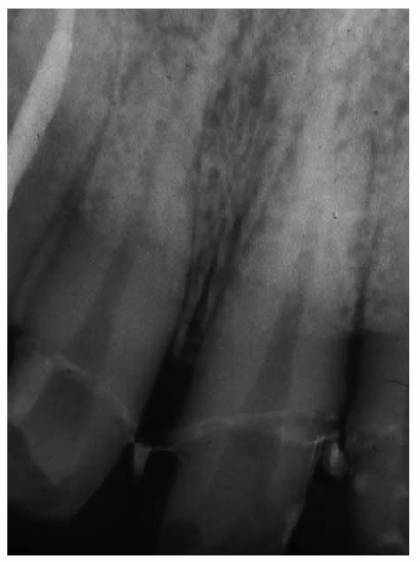

In most cases, an endodontic procedure should not be initiated without

evaluating at least two recent radiographs exposed at different horizontal

angulations of the suspected tooth (Figures 19-24A

and B).

Comparing varied views is essential in diagnosing the presence of additional

roots, anatomic configurations, anomalies, and other unusual circumstances that

may complicate the treatment.

Figure 19-24A and B: (A) Pretreatment radiograph of a mandibular premolar shows one canal. (B) A second radiograph taken from an angulation of 15 degrees from the mesial discloses a second root.